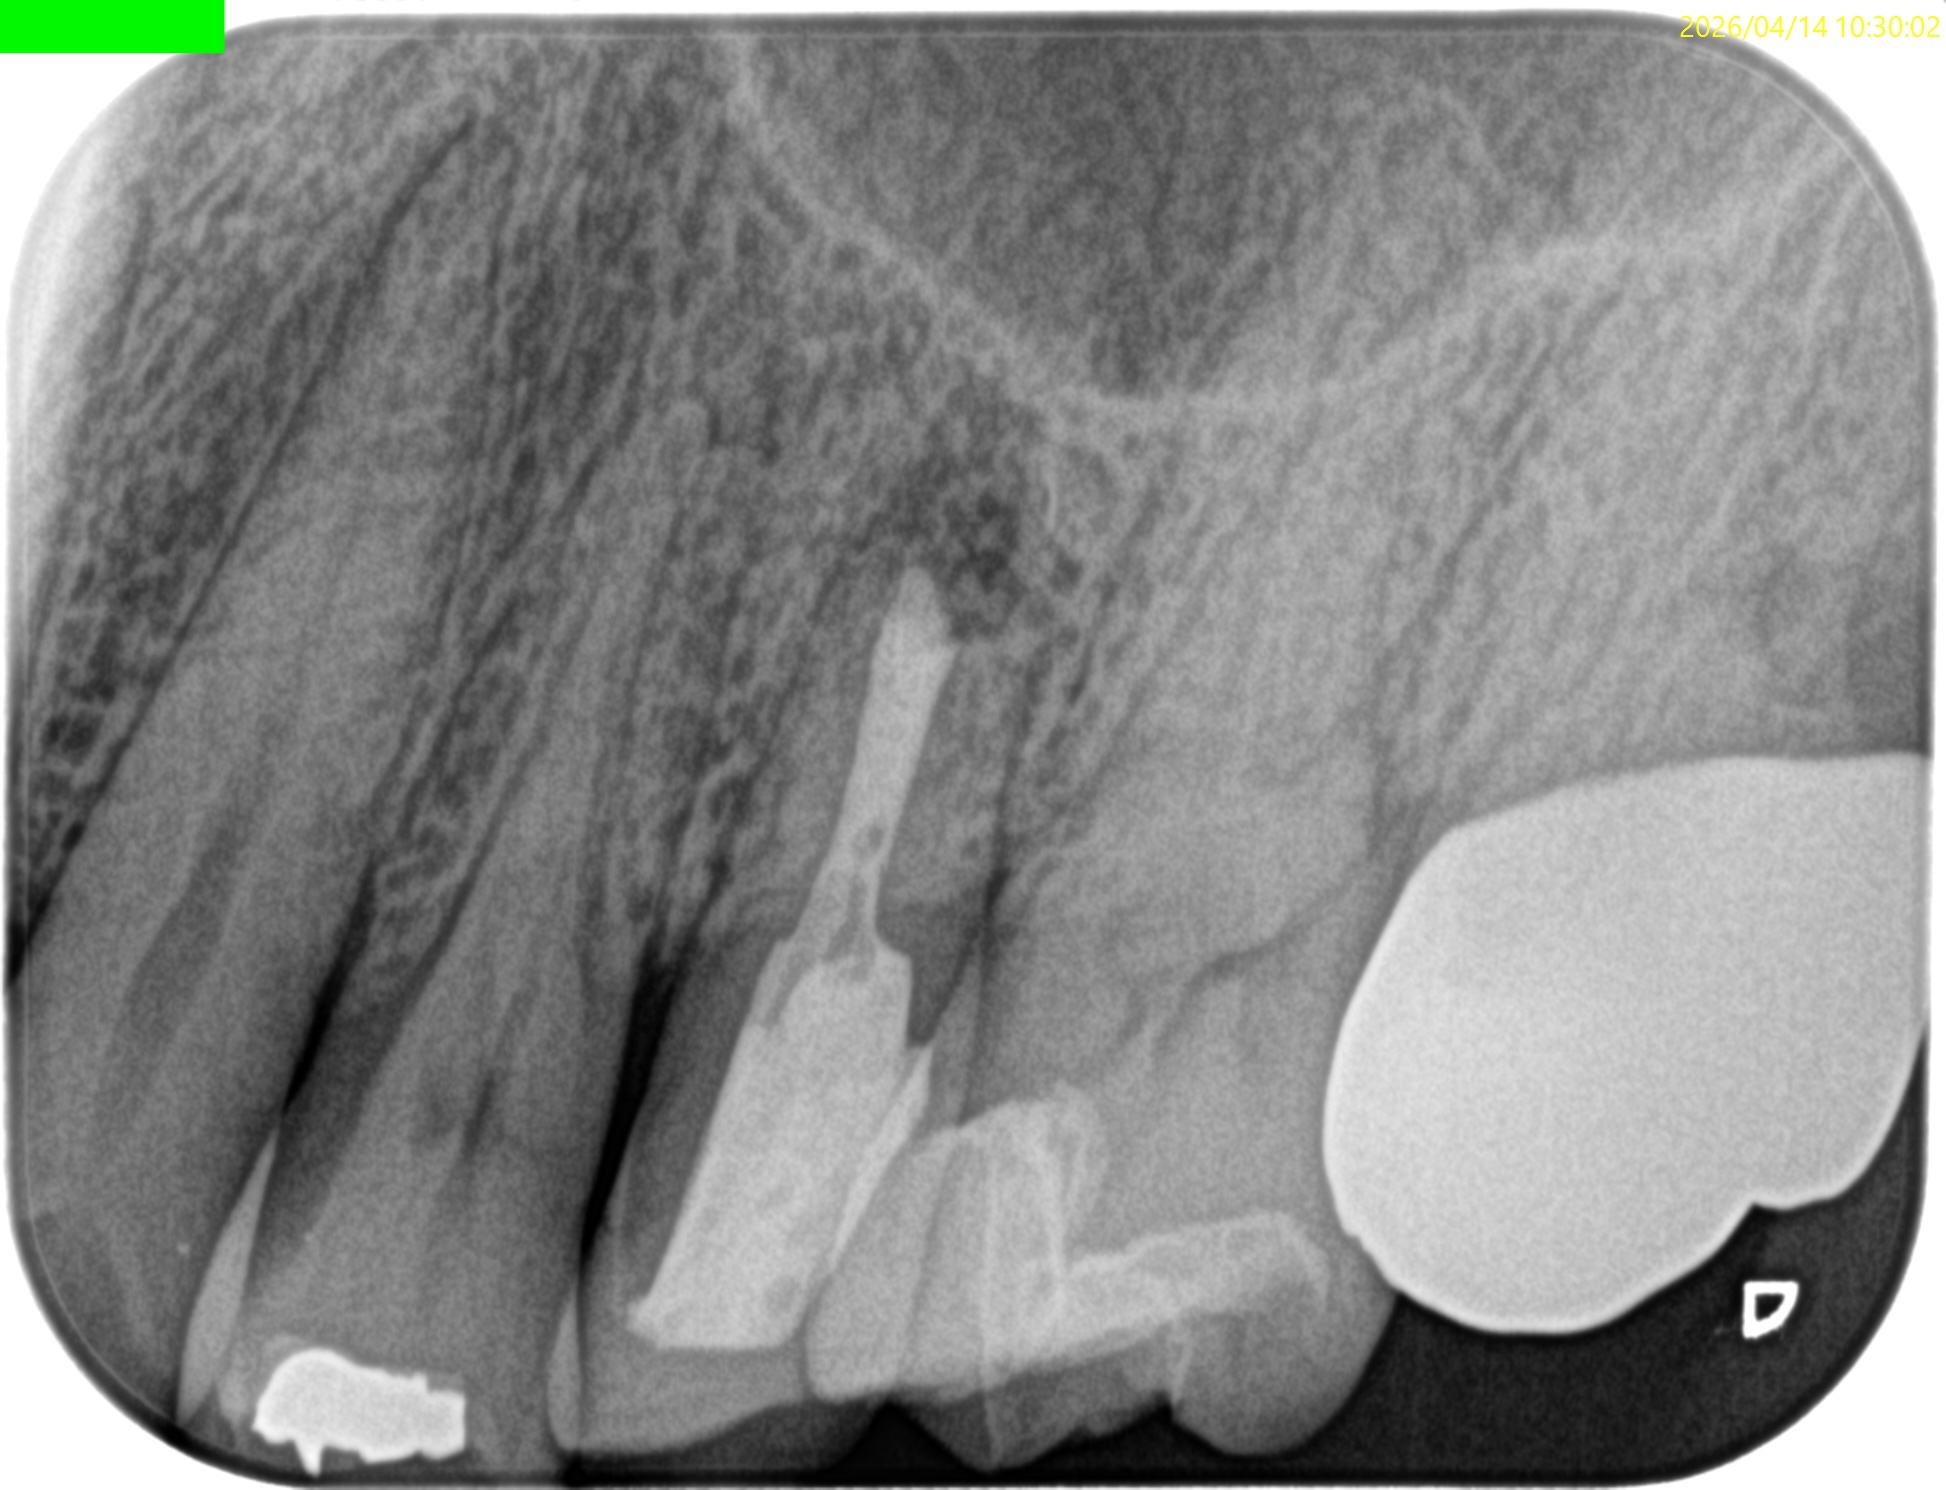

Pre-op Endo test(2026.4.6)

臨床症状はないが…

上顎洞炎は治癒したままだが、Lid TechniqueのLidごと材料が外れてしまっている。

#13 Re-Apicoectomy(2026.4.14)

術後にPA, CBCTを撮影した。